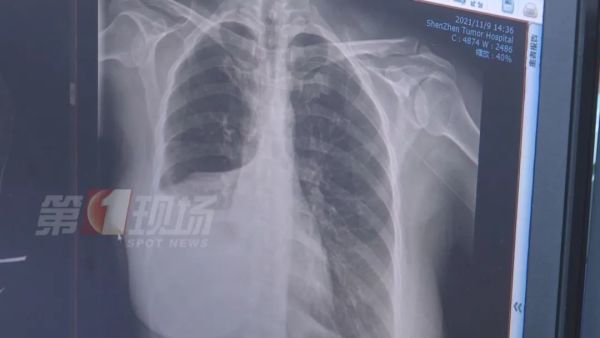

江女士做了增强CT后,确实发现肺部有一个五公分左右的肿瘤,医生诊断为肺癌,目前为中期偏早,建议她进行切除手术。